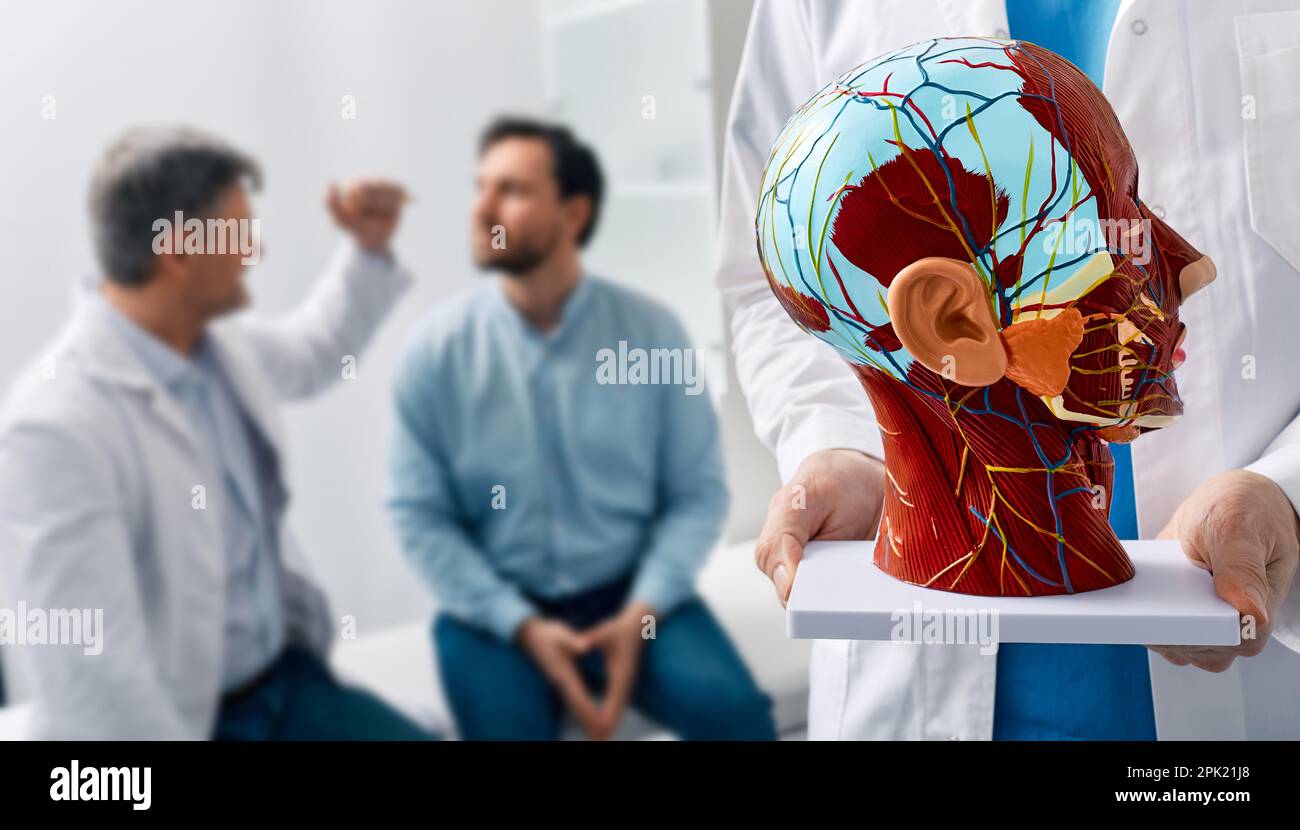

Neurology, conceptual image. Anatomical model of human head with vascular structures and nerves in foreground of neurologist's consultation with patie Stock Photohttps://www.alamy.com/image-license-details/?v=1https://www.alamy.com/neurology-conceptual-image-anatomical-model-of-human-head-with-vascular-structures-and-nerves-in-foreground-of-neurologists-consultation-with-patie-image545245072.html

Neurology, conceptual image. Anatomical model of human head with vascular structures and nerves in foreground of neurologist's consultation with patie Stock Photohttps://www.alamy.com/image-license-details/?v=1https://www.alamy.com/neurology-conceptual-image-anatomical-model-of-human-head-with-vascular-structures-and-nerves-in-foreground-of-neurologists-consultation-with-patie-image545245072.htmlRF2PK21J8–Neurology, conceptual image. Anatomical model of human head with vascular structures and nerves in foreground of neurologist's consultation with patie